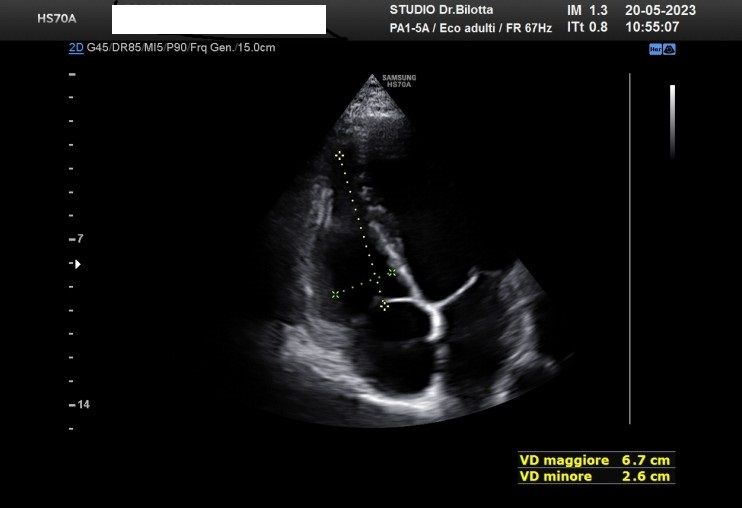

Diploma di maturità classica. Laurea in Medicina e Chirurgia con Lode a 26 anni. Specialista in Oncologia Generale Diagnostica e Preventiva con Lode a 31 anni. Specialista in Malattie Cardiovascolari a 36 anni. Medico generalista dal 1990 poi ospedaliero per trent'anni dal 1993 al 2022 nel corso dei quali ho refertato oltre 100 mila tracciati elettrocardiografici, effettuato oltre 30 mila consulenze specialistiche, praticato circa 10 mila esami ecocardiografici, condotto oltre 2 mila test ergometrici sia su cicloergometro che su treadmill, visionato circa 1500 esami Holter Ecg e ABP ( Ambulatory Blood Pressure ) occupandomi prevalentemente di prevenzione cardiovascolare, ipertensione arteriosa, cardiopatia ischemica, valvulopatie. Dal 2023 ho deciso di trasferire le mie competenze nella libera professione presso il mio studio privato che è stato allestito in linea alle moderne esigenze tecnologiche. Metodiche diagnostiche attualmente praticate: Elettrocardiografia a riposo, Ecocardiografia mono-bidimensionale, PW, CW, Colordoppler tridimensionale, GLS Strain Speckle tracking, Monitoraggio Holter Pressorio delle 24 ore, Monitoraggio Holter ECG 12 canali dinamico delle 24 ore.

Foto e video